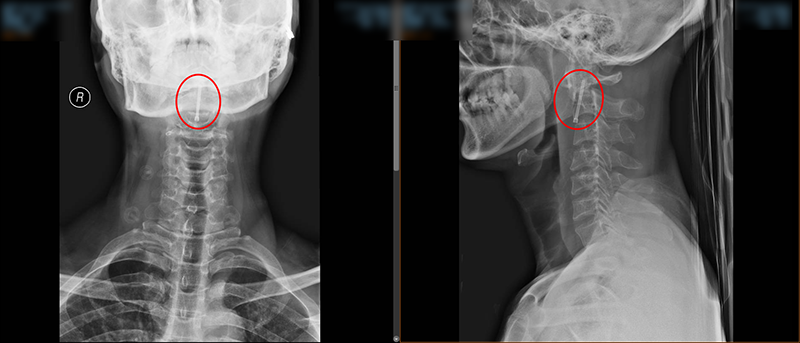

術(shù)中,脊柱外科團(tuán)隊(duì)對(duì)王先生頸部重要的組織結(jié)構(gòu)均進(jìn)行了較好的保護(hù),而且一次性成功的置入空心拉力螺釘固定骨折斷端。手術(shù)持續(xù)了45分鐘,術(shù)后王先生頸部疼痛明顯緩解,無神經(jīng)損傷。術(shù)后給予抗炎、補(bǔ)液等治療,在科室專業(yè)醫(yī)療、護(hù)理團(tuán)隊(duì)的共同努力下,術(shù)后復(fù)查X線顯示齒狀突復(fù)位,螺釘位置良好,目前已在支具輔助下行走活動(dòng),患者及家屬對(duì)手術(shù)效果非常滿意。

▲術(shù)后X線檢查結(jié)果